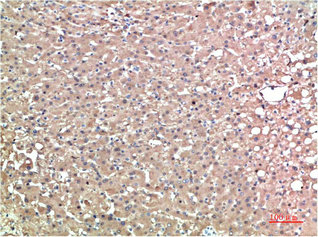

產(chǎn)品描述:TTR單克隆抗體(CUSABIO貨號(hào):CSB-MA263346)是經(jīng)重組蛋白免疫原制備的小鼠IgG型科研用抗體,專用于人源轉(zhuǎn)甲狀腺素蛋白的精準(zhǔn)檢測(cè)。該蛋白作為甲狀腺激素和視黃醇結(jié)合蛋白的載體,在淀粉樣變性發(fā)病機(jī)制研究中具有重要價(jià)值,其異常沉積與家族性淀粉樣多發(fā)性神經(jīng)病變密切相關(guān)。產(chǎn)品采用液體形態(tài)保存,建議長(zhǎng)期存放于-20°C或-80°C環(huán)境以保持穩(wěn)定性,適用于ELISA、Western Blot和免疫組化三大實(shí)驗(yàn)平臺(tái)。在蛋白質(zhì)相互作用分析、病理切片中TTR分布定位、以及疾病模型構(gòu)建等基礎(chǔ)研究中,該抗體可有效檢測(cè)內(nèi)源性TTR表達(dá)水平,為神經(jīng)退行性疾病和代謝紊亂研究提供可靠工具。通過(guò)優(yōu)化實(shí)驗(yàn)條件,該產(chǎn)品在膜轉(zhuǎn)印檢測(cè)中展現(xiàn)良好的特異性,適用于檢測(cè)分子量約15kDa的TTR蛋白,滿足科研人員對(duì)轉(zhuǎn)甲狀腺素蛋白功能驗(yàn)證、表達(dá)譜分析及信號(hào)通路研究的多元化需求。

應(yīng)用范圍:ELISA,WB,IHC

Application Recommended Dilution WB 1:500-1:5000 IHC 1:50-1:500 -